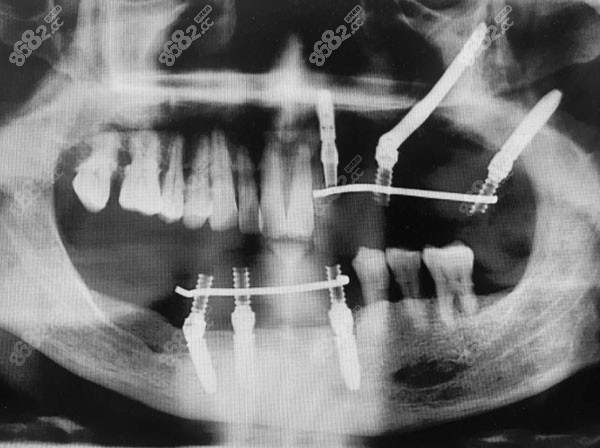

种植牙是医学界公认的理想修复方式,被誉为“人类的第三副牙”。但很多想种牙的人一看价格就望而却步了,种植牙需要多少钱呢?下面请参考北京康贝佳口腔种植牙价格表,看看康贝佳的种植牙收费到底高不高。

由北京康贝佳口腔的价格表可知,康贝佳口腔的种植牙收费不算高,和市场上的价格都差不多,其实正规口腔的种植牙价格都是不分上下的。而且像穿颧穿翼这类复杂的种植牙技术,北京康贝佳口腔都可以做~

北京康贝佳口腔穿颧穿翼

郭斌作为口腔医学博士,曾在上海市第九进修种植及口腔颌面外科,为韩国dio植体做技术支持。擅长种植及种植修复,即拔即种即刻修复,ALL-one-4,ALL-one-6全口种植是他的强项哦~

院长邱麟毕业于第四口腔医学博士,曾是种植医生,是瑞典Nobel、美国Bicon和韩国Osstem种植系统的授权医师,多次参加国内外口腔学术交流峰会,并受邀作微创种植专题报告并现场演示微创种植手术。邱麟医生高超的技术获得顾客的一致认可~

擅长项目:all-on-X即刻种植技术微创即刻种植即刻修复即刻负重技术数字化种植技术、各种牙槽骨缺损、骨增量技术全口/半口、无牙颌种植技术各种疑难杂症种植技术;失败种植修复的再治疗等技术。